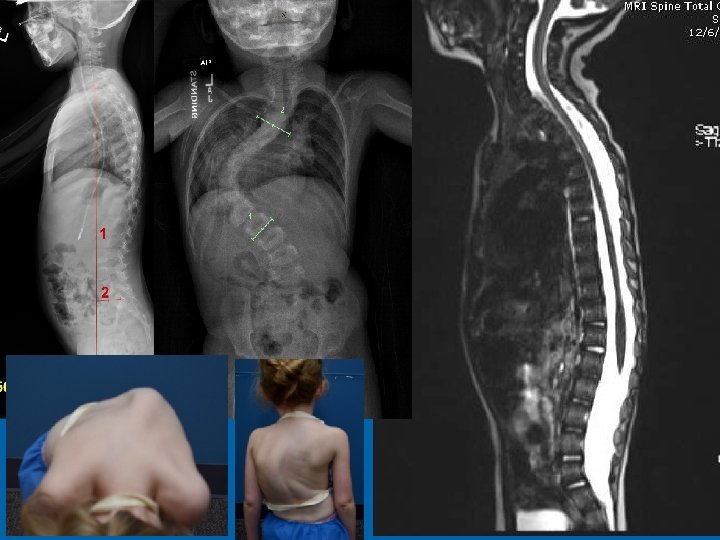

Progressive NF 1 Scoliosis August 12, 2013

August 12, 2013

27

NF 1 and Dural Ectasia • Frequently thoracic • Can be relatively protective, increased SAC • Posterior scalloping commonly associated with dural ectasia • Lateral and anterior scalloping commonly result of primary mesodermal dysplasia • Tsirikos AI 2004 • Anterior dural ectasia and dislocation of the spine • Winter 1991 28